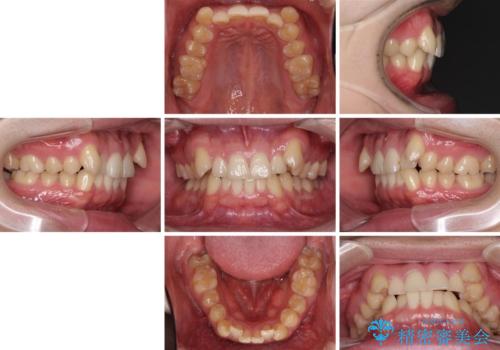

- 上顎の八重歯と前歯のデコボコを気にして来院された患者様です。

八重歯の移動量が多く、インビザライン単体での治療は困難と判断し、補助装置により八重歯移動後にインビザラインを用いることとしました。

治療途中で遠方に転勤となったため、通院が困難となり治療期間が長期化してしまいました。

上顎のみの抜歯矯正をインビザラインで行う場合、奥歯の前方移動がインビザラインでは苦手のため、奥歯の咬み合わせが不十分となることがあります。

今回の治療では終了時に奥歯は接触しているものの、接触の程度は物足りないものがある状態でした。今後保定期間に少しずつ奥歯の咬合を改善させていくことになります。